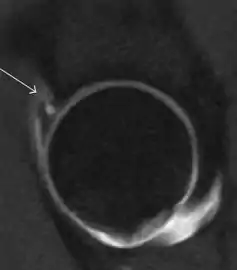

Synovial chondromatosis can be confidently diagnosed by X-ray when calcified cartilaginous chondromas are seen. However, other synovial proliferative processes, such as pigmented villonodular synovitis, require MRI for accurate diagnosis, although noncalcified synovitis can be suspected in radiographs by indirect signs, such as soft tissue swelling and/or erosions in the femoral head, femoral neck, or acetabulum (Figure 7).[1]

Figure 7:

- Axial CT image of pigmented villonodular synovitis eroding the posterior cortex of the femoral neck.[1]

- Sagittal T2* gradient echo image showing a posterior soft tissue mass with hypointense areas secondary to hemosiderin deposition.[1]

In synovial proliferative disorders, MRI demonstrates synovial hypertrophy. In the case of PVNS, characteristic foci of low signal intensity related to hemosiderin deposition are better seen on gradient echo T2* images (Figure 7). In the case of synovial osteochondromatosis, the synovial hypertrophy is accompanied by intermediate signal cartilaginous loose bodies and/or low signal calcified loose bodies.[1]